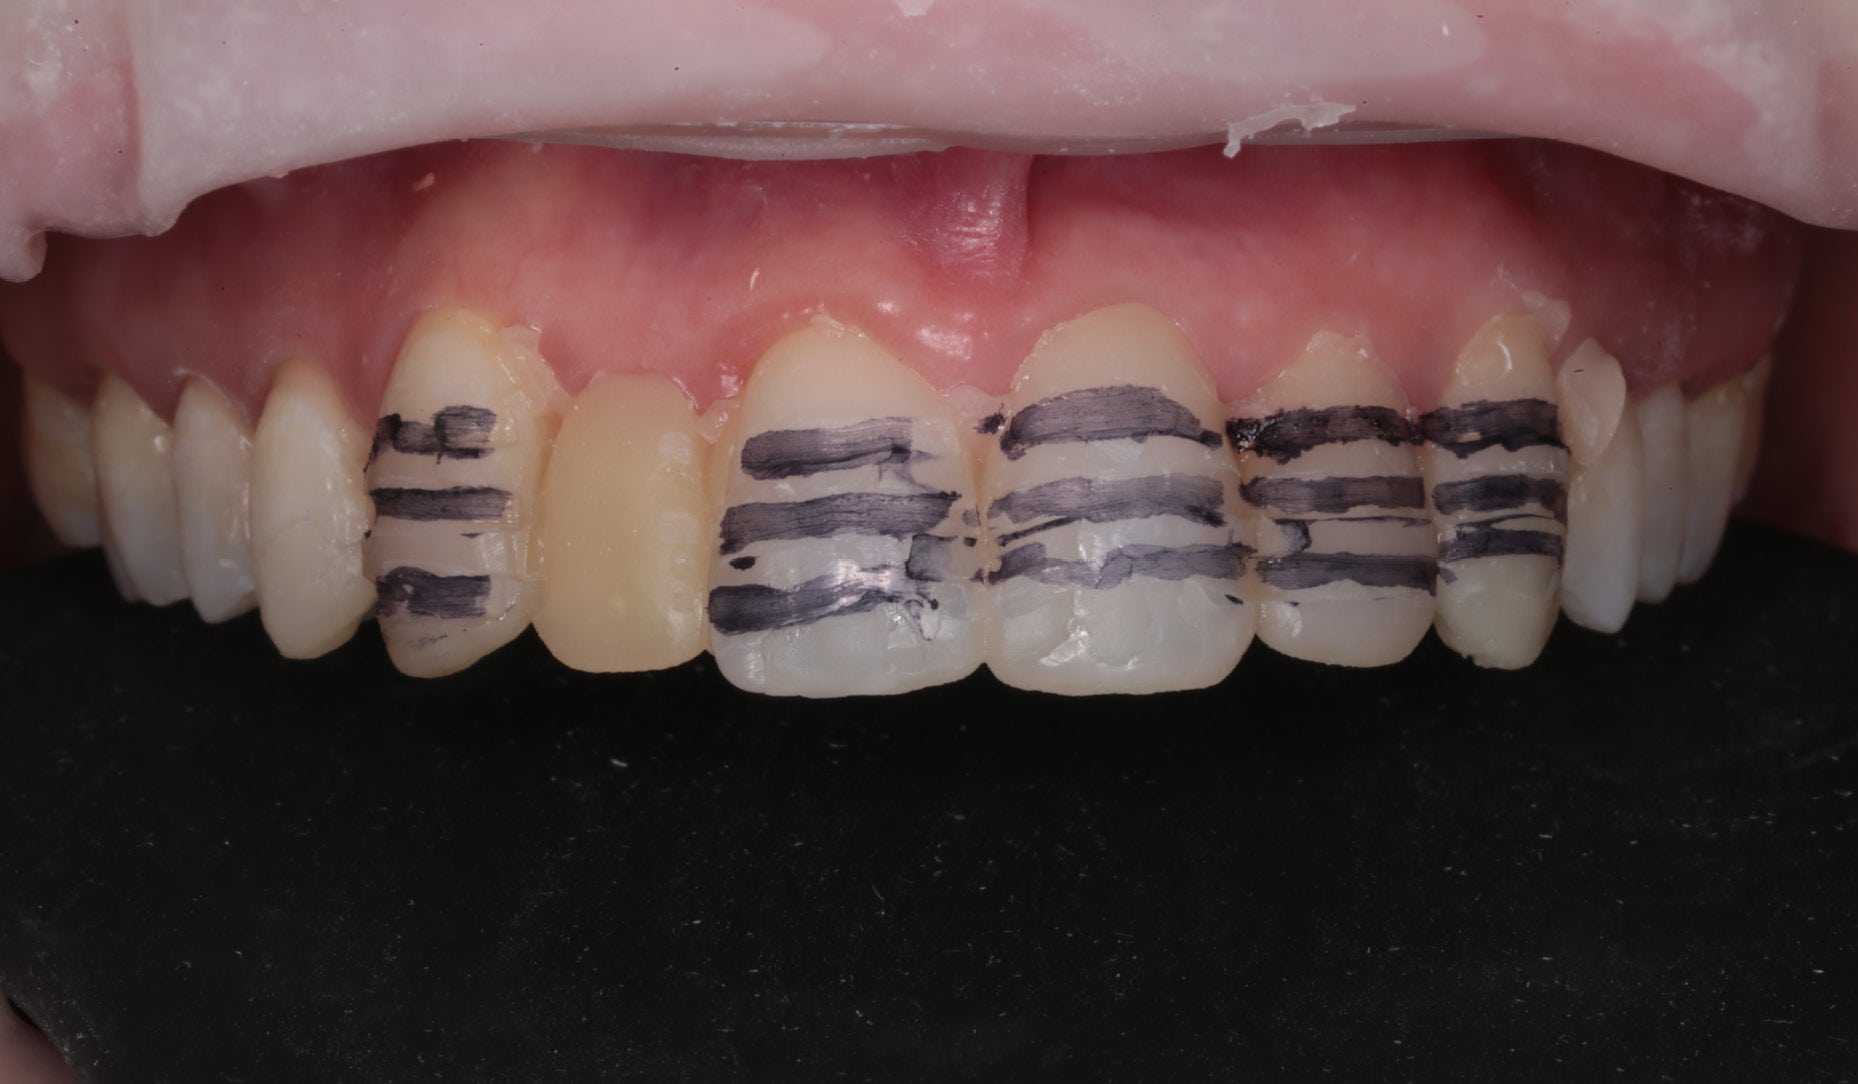

Clinical Cases, Labside Two high-strength ceramics, one micro-layering system Case by DT Andreas Chatzimpatzakis AESTHETIC AND EFFICIENT SMILE MAKEOVER Most patients asking for a smile makeover desire custom solutions rather than an off-the-peg smile: Individual tooth shapes that fit their face and their character, an internal play of colours that matches their age and natural dentition. Modern dental materials allow us to deliver what they demand in many situations – usually at a reasonable price. For a long time, however, we have been facing challenges when combining cosmetic and medically indicated treatment – e.g. a smile makeover including the rehabilitation of a missing lateral incisor. A straightforward solution – using lithium disilicate veneers alongside a zirconia cantilever bridge, both finished with their respective porcelain systems – would have been complicated by potential differences in the final appearance. With CERABIEN™ MiLai (Kuraray Noritake Dental Inc.), a set of internal stains and porcelains designed for micro-layering, the situation is different: Suitable for micro-layering on zirconia and lithium disilicate, it supports its user ideally in creating a harmonious smile even when the two framework materials are combined. A NEW CUSTOM SMILE The following patient case is a perfect example: A female patient with a missing lateral incisor, multiple visible composite restorations in the anterior region and an enamel fracture at her incisal edge desired a smile makeover. The selected materials were Amber Press LT (HASS), shade A1, for four veneers on the central incisors and the left lateral incisor and canine (teeth # 11, 21, 22 and 23 according to the FDI notation) and KATANA™ Zirconia YML (Kuraray Noritake Dental Inc.), shade A2, for the planned cantilever bridge on the maxillary right canine, replacing the missing lateral incisor (teeth # 12 and 13). Fig. 1. Female patient with a missing maxillary lateral incisor and multiple composite restorations in the anterior area – a smile makeover is desired. Fig. 2. Patient with mock-up. Fig. 3. Minimally invasive preparation through the mock-up, which takes into account the minimum space required for the planned materials and restorations. Fig. 4. Teeth prepared for the all-ceramic restorations. Fig. 5. Occlusal view of the maxillary teeth after tooth preparation. Fig. 6. Full-contour veneers and cantilever bridge on the model. Fig. 7. Restorations after a cutback limited to the vestibular and incisal area. Fig. 8. CERABIEN™ MiLai LT1 is applied to the middle and cervical area of the zirconia cantilever bridge. Fig. 9. CERABIEN™ MiLai Value Liner 2... Fig. 10. … and Value Liner 1 applied to the incisal area of the central and lateral incisor restorations. Fig. 11. CERABIEN™ MiLai porcelain Creamy Enamel mixed with Value Liner 2 (70/30) added to the middle and cervical areas of the four lithium disilicate restorations to increase and control the value. Fig. 12. ... while E2 is added to the incisal area of both canines. Fig. 13. Restorations covered by a layer of Tx ... Fig. 14. ... and LTx. Fig. 15. Appearance of the restorations after the first bake. Fig. 16. Adding translucency and opalescence to the cervical area with LT1 and brightness to the ridges with Creamy Enamel. Fig. 17. Completion of the enamel surface with a cover layer of LTx, which is responsible for a high translucency and opalescence. Fig. 18. Result of the second bake. Fig. 19. Final restorations with a natural self-glaze effect on the model. Fig. 20. Final restorations with a natural self-glaze effect in the patient’s mouth. Fig. 21. Smooth optical integration of the restorations. Fig. 22. Beautiful treatment outcome. CONCLUSION With the described approach and selected materials, it was possible to create restorations with a natural shade, shape and texture. They matched not only the appearance of the remaining natural teeth, but also showed internal consistency across the selected framework materials. The technical procedure was quite straightforward and efficient, while the result speaks for itself. Special thanks to Dr. Kanellos Ioannis for the collaboration on this case and for kindly providing the pre- and post-treatment photographs that complemented it. Dental technician: ANDREAS CHATZIMPATZAKIS Based in Athens, Greece, Andreas Chatzimpatzakis is the founder and director of ACH Dental Laboratory (since 2000), specializing in refractory veneers, lithium disilicate, zirconia, and implant prostheses. He graduated in Dental Technology from the University of West Attica and received advanced training in all-ceramic restorations in Helsinki and Japan under renowned masters including Shigeo Kataoka. Since 2017, he has served as an international trainer for Kuraray–Noritake Dental Inc., delivering lectures and hands-on courses worldwide on advanced ceramic techniques. He has also held roles as Key Opinion Leader for MPF Brush Co., Ambassador for Hass Co., and Editor-in-Chief of Laborama. An active member of the Hellenic Academy of Aesthetic Dentistry, his work and articles have been published in both Greek and international journals. Jan 21, 2026 Dental Technician Kuraray Noritake Prosthodontics Clinical Case Katana Zirconia YML CERABIEN MiLai Prosthetic dentistry Lab Dental Ceramics Cad Cam Discs KATANA Zirconia YML View Product CERABIEN MiLai View Product Subscribe to our Newsletter Join thousands of dental professionals and receive free advice that can help you and your career. We will not spam or share your e-mail.